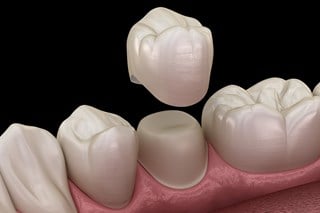

Behandlingar

Nedan finns en lista med behandlingar som vi utför. Klicka på knapparna för att läsa mer om just den behandlingstypen🦷